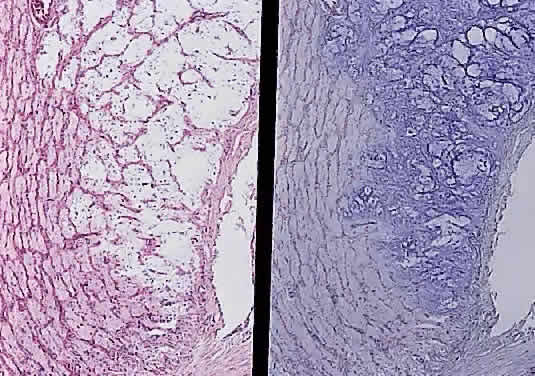

Grossly, optic gliomas that are confined to the orbit appear as fusiform, solid, and somewhat firm expansions of the optic nerve (Fig. 36). They usually blend imperceptibly with the grossly uninvolved nerve at either end. The enveloping dura may be stretched but is not breached. Microscopically, the tumor is composed of bipolar hair-like (pilocytic) astrocytes that infiltrate between preexisting axons and expand rather than compress the nerve fascicles. The neoplastic cells are only mildly atypical, and mitotic figures are typically absent. Not uncommonly, the tumor “spills over” into the subarachnoid space, forming a collar (Fig. 37).

Fig. 37. Pilocytic glioma of optic nerve (hematoxylin and eosin staining). Low power on left shows nerve surrounded by thickened meninges. High power on right shows spindle-shaped cells.